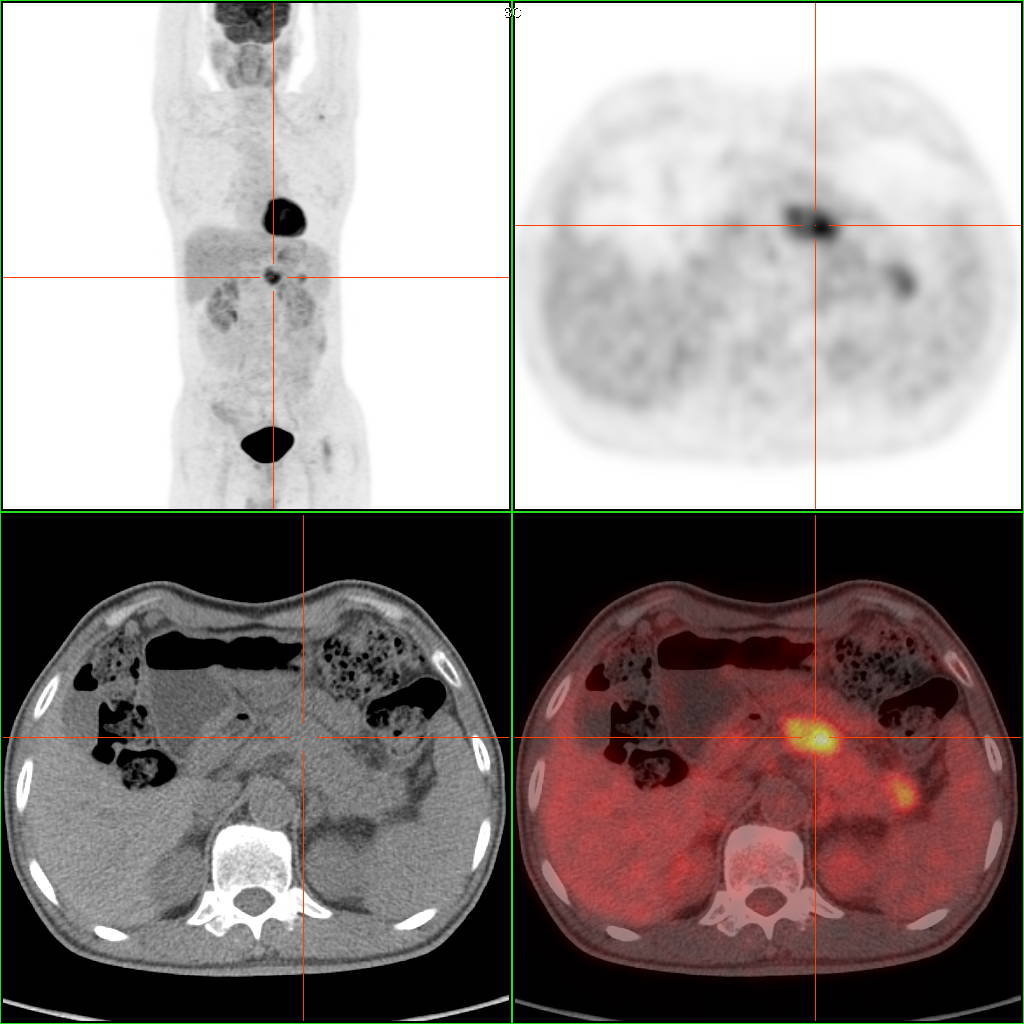

该病人无明显症状,CT检查发现胰腺头颈部稍丰满,无异常低密度改变,肿瘤标记物不高。PET/CT检 查明确诊断:胰腺头颈部早期胰腺癌。 PET/CT通过放射性示踪剂来检测组织的代谢活性,并结合CT的解剖信息,适合全身性的肿瘤检测和评估,显像剂到哪里,仪器就可以看到那个地方。

PET/CT不仅能够识别身体中的异常组织是否为肿瘤,还能评估肿瘤的阶段、定位肿瘤细胞在体内的分布、勾画放疗靶区、精准定位穿刺活检位置,并监测肿瘤治疗的效果。通过在治疗前后各进行一次PET/CT扫描,并将两次的影像资料进行对比分析,医生可以直观地观察到治疗效果,从而为制定或调整治疗计划提供重要依据。